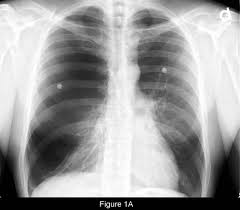

Bullous lung disease symptoms. There are several subtypes of emphysema including subcutaneous emphysema bullous. Group B GOLD 1 or 2. Most people with bullous emphysema experience shortness of breath wheezing coughing up phlegm and centralized pain in their chests especially when engaging in physical activity.

Some patients suffer from nausea loss of appetite and fatigue as a. Patients frequently present with nonspecific symptoms including intermittent wheeze and cough and these are often attributed to other conditions such as asthma and smoking-related COPD especially when there is concurrent heavy smoking history. As the disease progresses you may find it increasingly difficult to breathe and engage in daily activity.

Emphysematous bullae can cause many respiratory problems including shortness of breath. Your FEV 1 is between 50 and 80. The harmful effects of tobacco smoking especially with regard to the aetiology of chronic obstructive pulmonary disease are well documented3 Large emphysematous bullae may develop usually in the context of significant tobacco exposure over many years and tend to be associated with airway obstruction reduced gas transfer factor and diffusion coefficient and evidence of centrilobular.

This is condition which is characterized by abnormal and enlarged air spaces within the lungs.